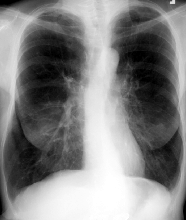

3.胸部X線診斷

(1)右下肺動脈乾擴張:橫徑>=1.5cm。經動態觀察後動脈乾橫徑增寬達2mm以上。

(2)肺動脈段凸出,高度>=3mm。

(3)中心肺動脈擴張與外周分支纖細兩者形成鮮明對比,呈“殘根狀”。

(4)右前斜位圓錐部凸出高度>=7mm。

(5)右心室增大(結合不同體位判斷)。具有(1)至(4)項中兩項以上或(5)1項者可診斷。

①肺部變化:隨病因而異,肺氣腫最常見。②肺動脈高壓表現:肺動脈總乾弧突出,肺門部肺動脈擴大延長及肺動脈第一分支。一般認為右肺動脈第一下分支橫徑≥15mm,或右下肺動脈橫徑與氣管橫徑比值≥0.17,或動態觀察較原右肺下動脈乾增寬2mm以上,可認為有該支擴張。肺動脈高壓顯著時,中心肺動脈擴張,搏動增強而外周動脈驟然變細呈截斷或鼠尾狀。③心臟變化:心臟呈垂直位,故早期心臟都不見增大。右心室流出道增大時,表現為肺動脈圓錐部顯著凸出。此後右心室流入道也肥厚增大,心尖上翹。有時還可見右心房擴大。心力衰竭時可有全心擴大,但在心力衰竭控制後,心臟可恢復到原來大小。左心一般不大,偶見左心室增大。心電圖查